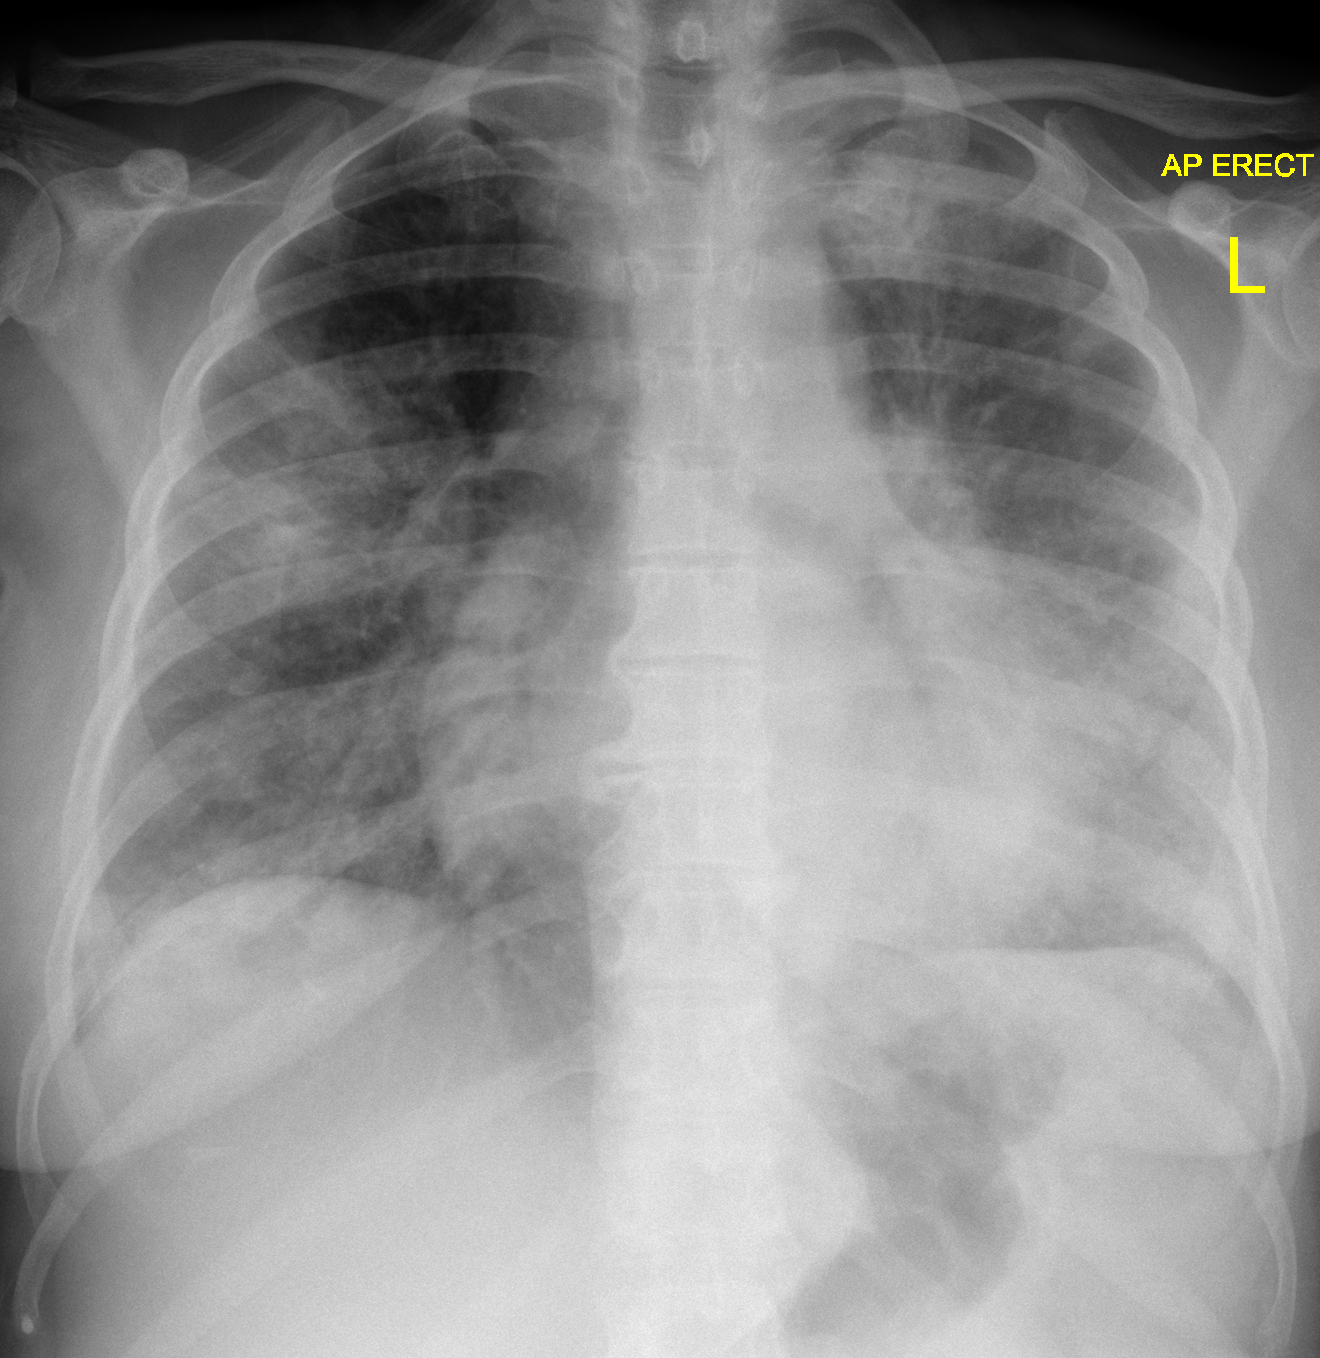

Diagnostic Methods

- Chest X-rays to identify lung inflammation

- Blood tests to detect antibodies against Legionella bacteria

- Urine tests to identify Legionella antigens

- Sputum culture to isolate the bacteria

The doctor will also do tests. The tests may include a chest X-ray, blood test, urine test, or looking at mucus from your lungs.